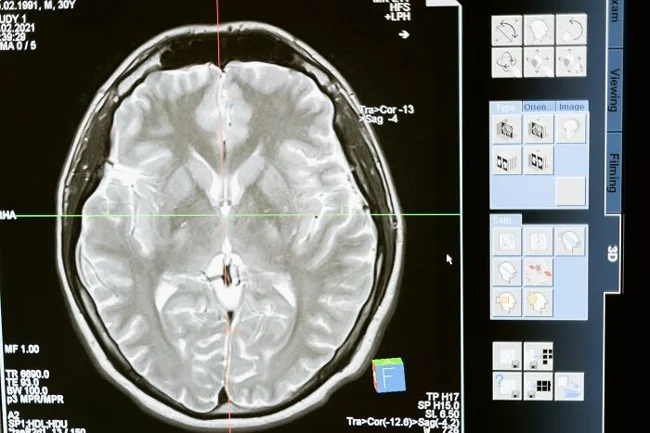

16. «Даже малейшая травма мозга может изменить всю твою жизнь. В зависимости от того, какая часть мозга пострадала, можно лишиться особых/основных чувств, контроля над собственным телом, способности использовать и/или понимать язык, воспоминаний, личности и т. д. Не забывайте надевать шлем, люди!».